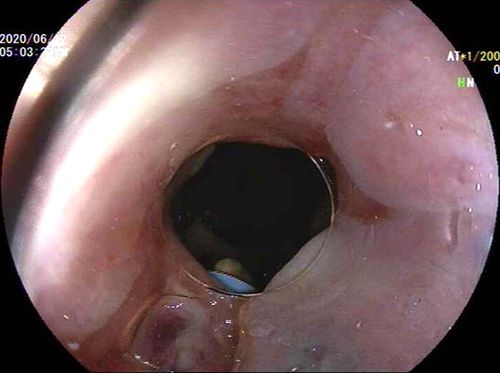

近期,我院内六科胃肠镜室成功开展了多例内镜下内痔痔上粘膜套扎术治疗内痔出血或脱垂,术后患者便血及内痔脱垂即刻消失,效果显著。

病例回顾:一名因内痔出血致重度贫血的老年男性和一名多年被内痔脱垂影响排便及反复便血不适而苦恼的老年女性病人,近期分别到我院内六科就诊。经医生详细检查后,均予行内镜下痔上粘膜套扎术治疗,术后患者便血及内痔脱垂即刻消失,术后观察1日均好转出院,术后1个月复查均无并发症,患者及家属非常满意。

经内镜痔上粘膜套扎术是个相当成熟的技术,目前已成为Ⅰ—Ⅲ°内痔及部分混合痔内痔部分首选治疗方式,特别对内痔脱垂及出血方面具有显著的效果。该手术疗效确切,费用低,保留了肛垫正常组织结构,复发率低且明显降低了传统外科手术的并发症,手术时间短,全程无需麻醉,无疼痛感,术后仅有肛门坠胀感及部分排尿困难,热敷后可缓解,术后当晚禁食及卧床休息6小时,次日即可进食及下床活动,术后观察1-2日即可出院。(内六科)